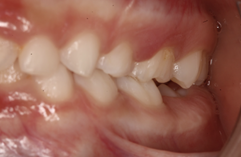

La relación molar tanto del lado derecho como del izquierdo se clasifica como Clase I, indicando una correcta intercuspidación molar y oclusión funcional bilateral. Esto sugiere un buen equilibrio dentoalveolar y favorece la estabilidad oclusal general.

Figura 7. Relación molar derecha Figura 8. Relación molar izquierda